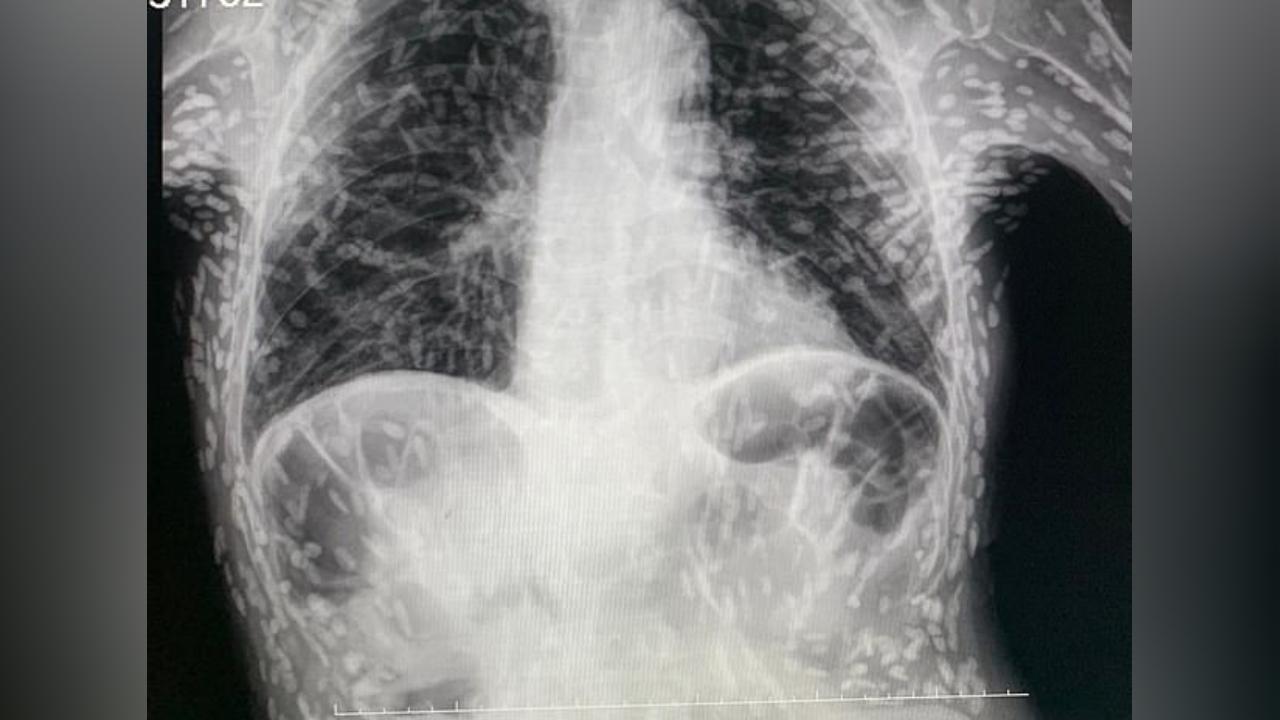

Xəstənin rentgenoqrafiyasında yüzlərlə ağ ləkə aşkar edilib. Bu ağ ləkələr parazitlərin kalsifikasiya olunmuş qalıqları olduğu ortaya çıxdıb.

Xəstədə donuz tapewormunun gənc formasının səbəb olduğu sistikerkoz adlı toxuma infeksiyası olduğu anlaşılıb.

Normalda bağırsaqlarda yaşayan lent qurdlarının sistierkoz zamanı əzələ və beyin kimi toxumalara daxil olduğu məlumdur. Tapeworms daxil olduqları bu toxumalarda kist kimi şişliklərə səbəb olur.